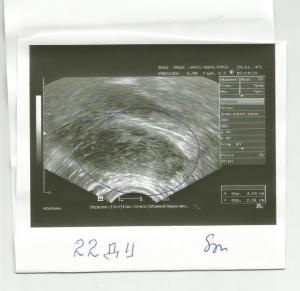

Овуляция( тесты на овуляцию)Добрый день! Помогите кто может разобраться! Сегодня 23 день цикла. Планируем ляльку. 7 месяцев назад была ВБ, удалили правую трубу. Сейчас как раз заработал левый яичник. На 10 ДЦ врач на УЗИ увидела два доминантных фолликула - 12 и 15 мм. Пришла повторно через неделю на 17-й день! И уже увидела только один и всего 13 на 15 мм. И остальные маленькие по 5-6 мм. Куда делся второй неизвестно. Сказала - овуляции наверное уже не будет. Потому что растет медленно очень. Я расстроилась невозможно. Так надеялись на этот цикл. БТ я мерить стала в этом цикле только дня с 15-го по-моему. И непонятно почему она стала подниматься с 16 дня. Опустилась на пару дней до 36,5 три дня назад. И низ живота сильно тянуло в этот день. Я испугалась и вчера помчалась опять на УЗИ. И она была крайне удивлена, глянув в монитор. У меня исчез и этот филликул. НЕТ ЕГО И ВСЁ! И жт не видно. Вчера сдала прогестерон 36,29. Норма в этой лаборатории до 27. Позавчера еще ТТ поднялась, 37,0. Держалась два дня. Насморк сильный и глаза слезились. Сегодня получше. Что со мной может быть?! Буду рада всем советам и поддержке!